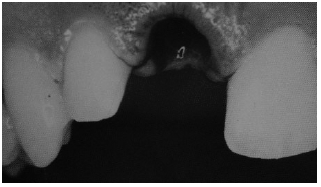

Diseases of the pulp can be secondary to trauma or operations, but clearly the most common cause is secondary to bacterial invasion after the carious destruction of the enamel. As enamel is destroyed, caries development progresses rapidly through the dentin and into the pulp chamber, causing an inflammatory reaction termed pulpitis. If the erosion caused by the bacteria is large enough to drain the developing inflammation, the patient may remain asymptomatic for a long period of time. When the drainage becomes blocked, the process progresses to the pulp and the periapical space, causing exquisite tenderness. A periapical abscess will follow the path of least resistance, which may be through the alveolar bone and gingiva and into the mouth or into the deep structures of the neck. (See Figure 11.) If the infection has progressed apically through the alveolar bone and there is localized swelling and tenderness at the base of the tooth, incision and drainage is indicated. These abscesses usually are seen at the gingival margin. Incision and drainage is performed easily by making a stab incision with a #11 blade over the area of maximal fluctuance. Small abscesses do not require a drain to be placed; however, large abscesses may benefit from a drain. A fenestrated drain or a piece of 1/4" gauze is acceptable and should be tacked to the mucosa with silk suture to prevent aspiration. Antibiotics that cover oral flora are prescribed.

| Figure 11. Deep Space Infections |

|